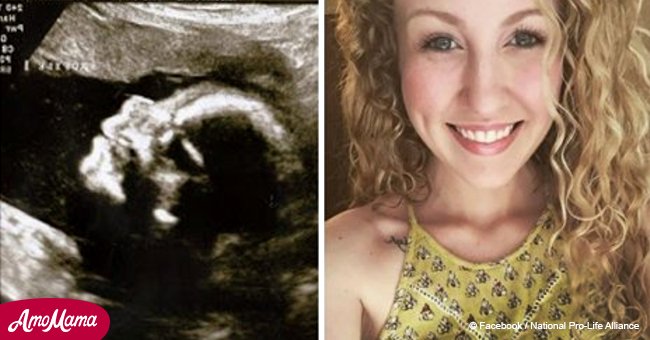

„Bored Daddy“ berichtete, dass Katie Whiddon hat auf dem Weg zum Ultraschall gehofft, dass der Arzt ihr gute Neuigkeiten vermitteln wird. Leider erwartete sie dort eine böse Überraschung.

Für die werdende Mutter war das eine wundervolle Zeit. Zudem konnte sie endlich herausfinden, welches Geschlecht das Baby haben wird. Katie hat sich so sehr ein Mädchen gewünscht.

Leider hatte der Arzt schlechte Neuigkeiten für sie. „Das, was ich da sehe, ist nicht gut. Alles ist sehr schlecht…“ sagte der Arzt.

Whiddot trug einen Jungen unter dem Herzen, aber das Problem war, dass dem Kind alle vier Gliedmaßen fehlten – seine Arme enden, wo sonst der Ellenbogen sein würde. Bei dem Kleinen wurde eine äußerst seltene Erbkrankheit Tetraamelie und Phokomelie-Syndrom diagnostiziert.